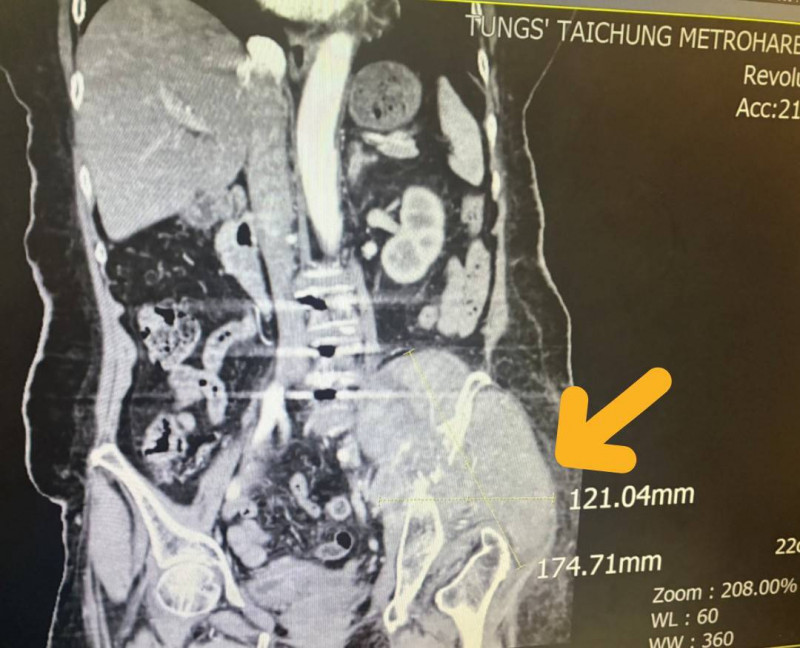

由於張婦的腫瘤細胞太大(約12.1公分x17.4公分),且腫瘤位置執行手術風險過高,葉啟源採用銳視刀適應性放射治療,利用空間分割點狀治療方式, 局部給予點狀高劑量的放射線,以高劑量消融巨大、抗放射性腫瘤,再配合傳統銳視刀,即以傳統劑量梯度保護周圍的健康組織與器官,經過1個月26次治療後,腫瘤縮小至9.8公分x10.1公分,緩解骶叢神經受壓迫的情況,疼痛明顯改善,也改善患者的行動能力。